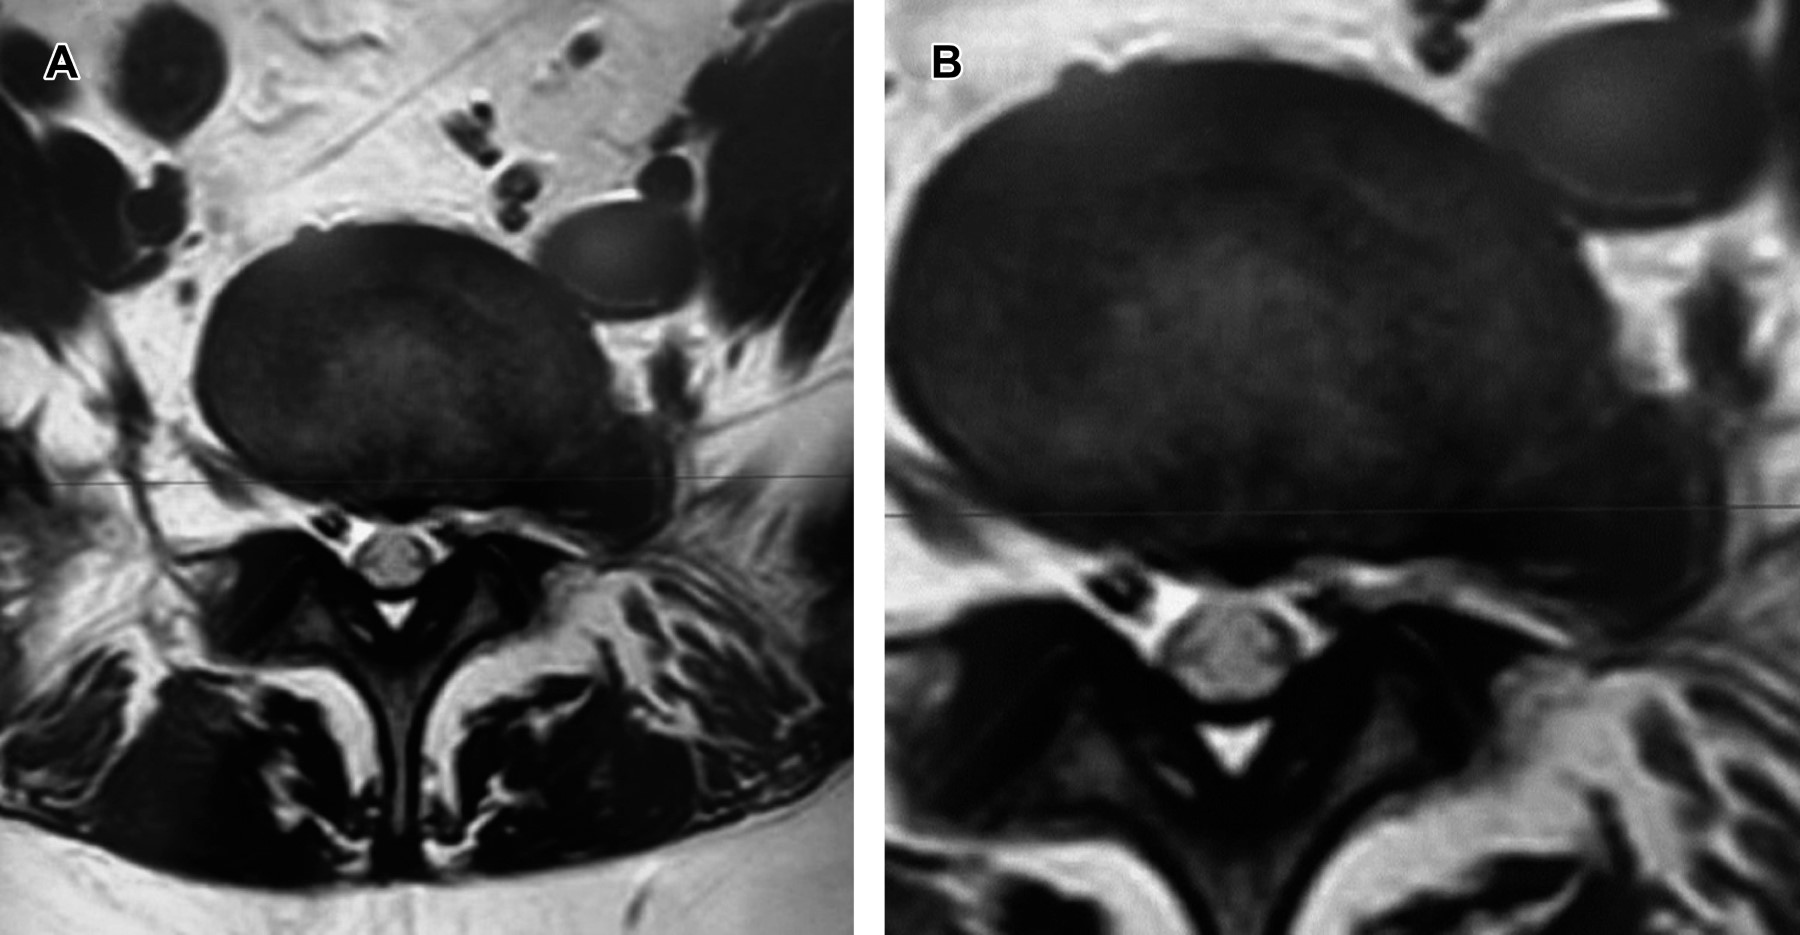

Femenino de 21 años, quien ocho días antes inició con dolor ciático izquierdo incapacitante para la ambulación. A la exploración: hipoestesia en territorio L4 izquierdo, Laségue positivo izquierdo a 10°; reflejo patelar izquierdo disminuido, Aquíleo normal; llenado capilar y pulsos normales. La resonancia magnética mostró disco extraforaminal L5/S1 con migración lateral "extrema" izquierda.

Se intervino quirúrgicamente mediante hemilaminectomía con foraminotomía izquierda L5, encontrando a la raíz normal en todo su trayecto, se retiró parcialmente la faceta L4/L5, encontrando el disco extruido en la parte inferior interna de la raíz L4, se retiró el disco extruido en su totalidad, dejando a la raíz libre. La evolución mostró desaparición total del dolor y se dio su alta 24 horas después (Figuras 1 y 2).

Figura 1